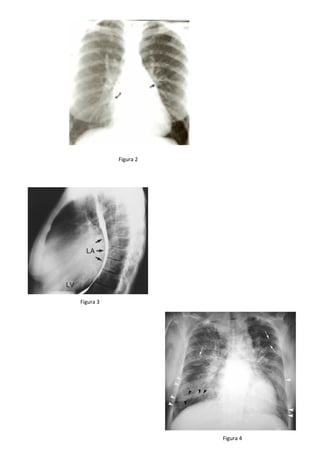

• Telerradiografia de tórax

o PA

– Duplo contorno na silhueta direita do coração.

– Sinal da bailarina (deslocamento superior do brônquio fonte E)

– Abaulamento do 40

arco cardíaco esquerdo (Figura 2)

o Perfil

– Deslocamento posterior do esôfago contrastado (Figura 3)

o Alterações pulmonares

– Inversão do padrão vascular

– Linhas B de Kerley (Figura 4)

– Edema intersticial.